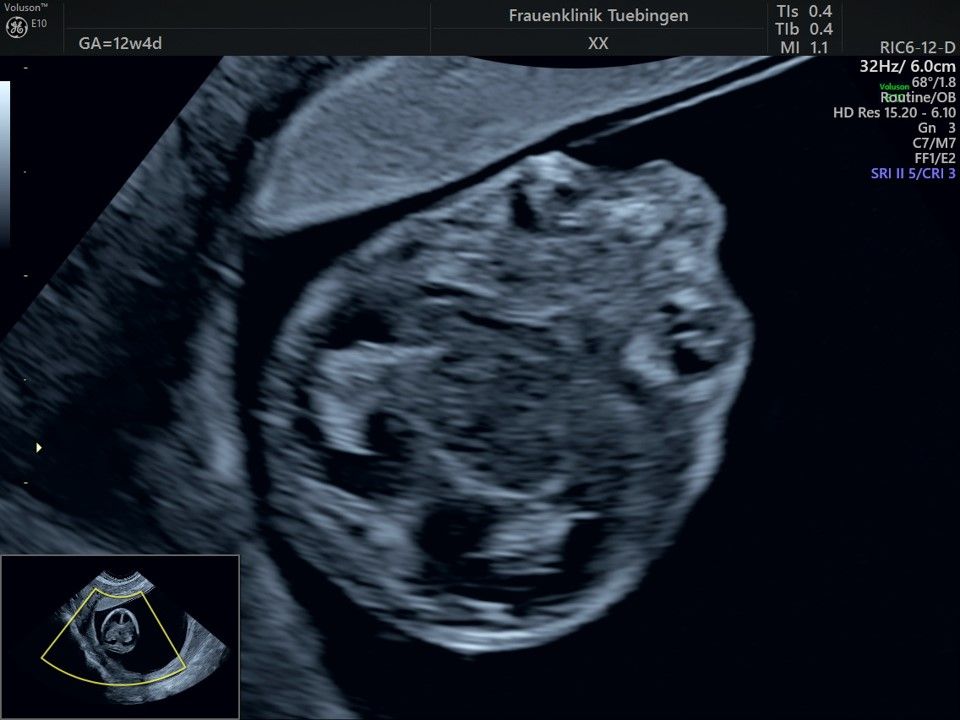

Im Rahmen des Ersttrimester-Screenings untersuchen wir die Organe des Feten mittels Ultraschall. Dabei machen wir auch gerne ein Bild für Sie.

Obwohl der Fet zu diesem Zeitpunkt erst zwischen 5 und 8cm groß ist, lassen sich bereits etwa die Hälfte aller schwerwiegenden Fehlbildungen erkennen bzw. ausschließen. Sollten wir eine Auffälligkeit sehen, werden wir mit Ihnen den Befund und das weitere Vorgehen ausführlich besprechen.

Bauchwanddefekt

Das Ergebnis der Ultraschalluntersuchung ist wegweisend. Dabei wird der Fet vermessen, die Organe werden untersucht und die sonographischen Marker zur Risikoberechnung für Chromosomenstörungen werden beurteilt. Das sind: die Nackentransparenzdicke, Nasenbein sowie der Blutfluss in der rechten Herzhälfte und im Ductus venosus, einem Gefäß in der Leber des Feten.